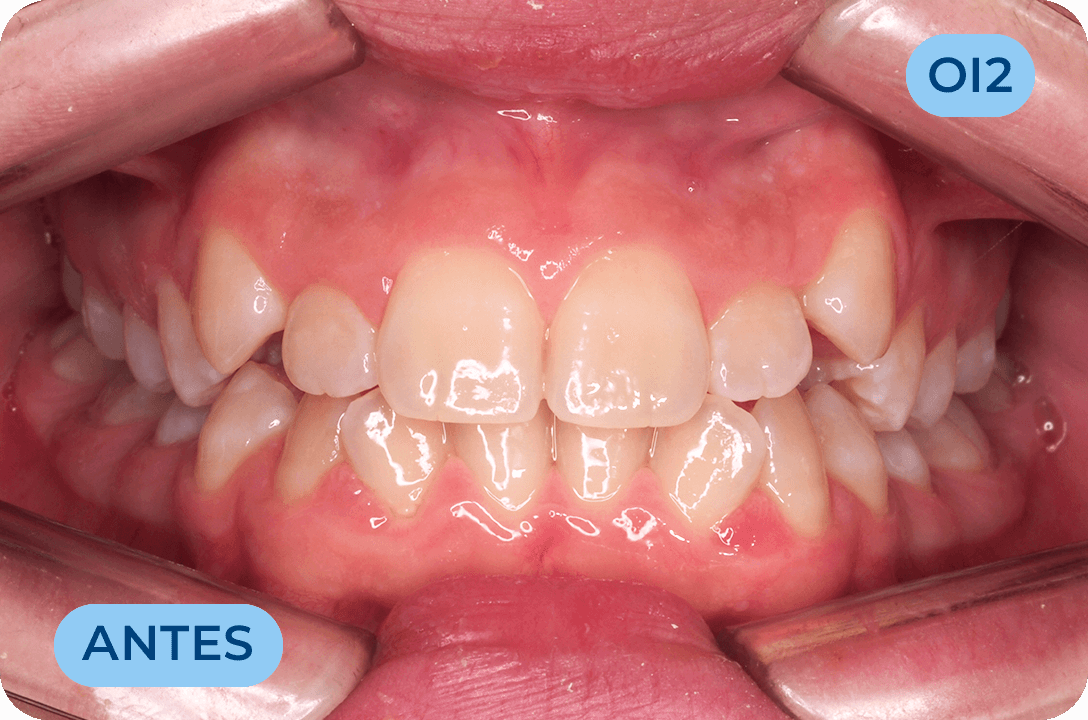

Ortodontia

É a especialidade da Medicina Dentária que se debruça sobre o estudo e correção das más posições dentárias e dos maxilares. Atualmente é possível tratar pacientes de todas as idades, no entanto a 1ª consulta deve ser realizada ainda na infância para intercetar eventuais problemas de desenvolvimento esquelético e funcional.